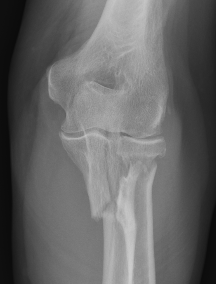

Definition

Elbow dislocation + olecranon fracture + radial head/neck fracture +/- coronoid fracture

Proximal ulna / olecranon fracture

- posterior radial head dislocation most common in adults

- no fractures